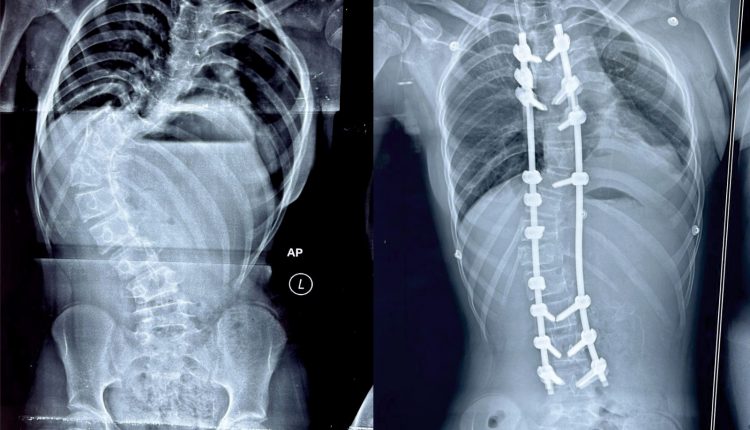

ଭୁବନେଶ୍ୱର: ମେରୁଦଣ୍ଡ ବଙ୍କା ହୋଇଯାଇଥିବା ଜନୈକା ବାଳିକାଙ୍କଠାରେ ସଫଳ ଅସ୍ତ୍ରୋପଚାର ଏହାକୁ ସଳଖ କରି ପାରିଛନ୍ତି କିମ୍‍ସର ଡାକ୍ତର। ସ୍କୋଲିଓସିସ୍ ନାମକ ଗୁରୁତର ମେରୁଦଣ୍ଡ ସମସ୍ୟା ସହ ଦୀର୍ଘ ଦିନ ଧରି ସଂଘର୍ଷ କରୁଥିବା ଏହି ବାଳିକାଙ୍କ ଅଭିଭାବକ ବହୁ ଖ୍ୟାତି ସମ୍ପନ୍ନ ଡାକ୍ତରଖାନାରୁ ନିରାଶ ହୋଇ ଶେଷରେ କିମ୍‍ସ ଡାକ୍ତରଙ୍କ ସହ ପରାମର୍ଶ କରିଥିଲେ।

ଅସ୍ଥିଶଲ୍ୟ ବିଶେଷଜ୍ଞ ତଥା ସ୍ପାଇନ୍ ସର୍ଜନ ଡା ଜିତେନ୍ଦ୍ର କୁମାର ରାଉତ ରୋଗୀଙ୍କୁ ଦେଖିବା ପରେ ଏହା ‘ଇଡିଓପାଥିକ ସ୍କୋଲିଓସିସ୍‌’ ନାମକ ଏକ ପ୍ରକାର ମେରୁଦଣ୍ଡ ସମସ୍ୟା ବୋଲି ଜାଣି ତୁରନ୍ତ ଅସ୍ତ୍ରୋପଚାର ପାଇଁ ପରାମର୍ଶ ଦେଇଥିଲେ। ନିଶ୍ଚେତକ ବିଭାଗର ଡା ସଞ୍ଜୀବ ଗିରି ଓ ରାଜ ମୋହନଙ୍କ ସହଯୋଗରେ ସ୍ପାଇନ୍ ସର୍ଜନ ଡା ରାଉତ ଏହି ଅସ୍ତ୍ରୋପଚାର କରିଥିଲେ।

ବାଳିକାଙ୍କ ମେରୁଦଣ୍ଡ ଇଂରାଜୀ ଅକ୍ଷର ‘ଏସ୍‌’ ଆକୃତିର ହୋଇଯାଇଥିଲା, ଯାହା ଭବିଷ୍ୟତରେ ତାଙ୍କ ପାଇଁ ଆହୁରି ଅନେକ ସମସ୍ୟା ସୃଷ୍ଟି କରିଥାନ୍ତା ବୋଲି ଡା. ରାଉତ ପ୍ରକାଶ କରିଛନ୍ତି। କିମ୍‌ସରେ ଦକ୍ଷ ଡାକ୍ତର, ଉନ୍ନତ ଜ୍ଞାନକୈଶଳ ଓ ଯନ୍ତ୍ରାଂଶ ଉପଲବ୍‍ଧ ଯୋଗୁଁ ଏଭଳି ବିରଳ ମେରୁଦଣ୍ଡ ଅସ୍ତ୍ରୋପଚାର ସମ୍ଭବ ହୋଇପାରିଲା। ସେ ବର୍ତ୍ତମାନ ସମ୍ପୂର୍ଣ୍ଣ ସୁସ୍ଥ ହୋଇଛନ୍ତି। କିଛି ଦିନ ବିଶ୍ରାମ ପରେ ସେ ସ୍ୱାଭାବିକ ଜୀବନଯାପନ କରିପାରିବେ ବୋଲି ଡାକ୍ତର ରାଉତ କହିଛନ୍ତି।

ସୂଚନାଯୋଗ୍ୟ, ପ୍ରଥମଥର ପାଇଁ ଓଡ଼ିଶାର ଏକ ଘରୋଇ ହସ୍ପିଟାଲରେ ଏଭଳି ଜଟିଳ ମେରୁଦଣ୍ଡ ଅସ୍ତ୍ରୋପଚାର କରାଯାଇ ପାରିଛି। ଏଭଳି ବିରଳ ଅସ୍ତ୍ରୋପଚାର କରି ‘କିମ୍‌ସ’ ରାଜ୍ୟର ଉନ୍ନତ ସ୍ୱାସ୍ଥ୍ୟସେବା ପ୍ରଦାନକାରୀ ଅନୁଷ୍ଠାନ ଭାବେ ପ୍ରମାଣିତ କରିପାରିଛି। ଏହି ମେରୁଦଣ୍ଡ ଅସ୍ତ୍ରୋପଚାର ସାଧାରଣତଃ ୭-୮ ଘଣ୍ଟା ସମୟ ଲାଗିଥାଏ, କିନ୍ତୁ କିମ୍‌ସର ସ୍ପାଇନ ସର୍ଜନ ତଥା ଓଡ଼ିଶା ସ୍ପାଇନ ସଂଘର ସମ୍ପାଦକ ଡା. ରାଉତ ଏବଂ ତାଙ୍କ ଡାକ୍ତରୀ ଦଳ ମାତ୍ର ୪ ଘଣ୍ଟାରେ ଏହି ସଫଳ ଅସ୍ତ୍ରୋପଚାର କରିପାରିଥିଲେ।